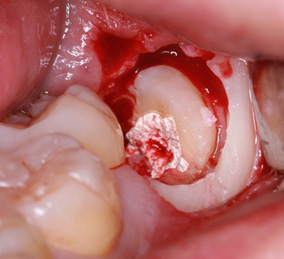

親知らずの歯根の先端と下顎神経が近接している場合は2回に分けて抜歯を行うことがあります。まず、親知らずを2分割して頭の部分を抜きます。その後しばらく期間をおいて、のこる歯根の部分が頭を抜いたスペースに移動したのを確認して抜きます。

このように2回に分ける事で安全な抜歯が可能です。

まず歯冠を切除し、疼痛がでないよう、冠部歯髄を除去してネオダイン(歯髄の鎮痛鎮静、象牙質の消毒、覆髄)を填入します。その後、粘膜骨膜弁にて完全閉鎖を行います。以下に処置の流れを示します。

歯冠切除量と歯根の移動量の結果です。術前の智歯(親知らず)の幅径に対して計測した智歯の長径の割合は1.21ポイント、術後は1.10ポイントで有意に差を認めました。数ヵ月待機することにより歯根は有意に近心側に移動していることを認めました。